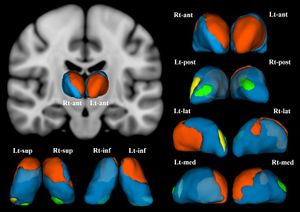

Thalamic Shape and Volume Abnormalities in Female Patients with Panic Disorder

Publication: PLoS One. 2018 Dec 19;13(12):e0208152. PMID: 30566534 | PDF Authors: Asami T, Yoshida H, Takaishi M, Nakamura R, Yoshimi A, Whitford TJ, Hirayasu Y. Institution: Department of Psychiatry, Graduate School of Medicine, Yokohama City University, Yokohama, Japan. Abstract: The thalamus is believed to play crucial role in processing viscero-sensory information, and regulating the activity of amygdala in patients with panic disorder (PD). Previous functional neuroimaging studies have detected abnormal activation in the thalamus in patients with PD compared with healthy control subjects (HC). Very few studies, however, have investigated for volumetric abnormalities in the thalamus in patients with PD. Furthermore, to the best of our knowledge, no previous study has investigated for shape abnormalities in the thalamus in patients with PD. Twenty-five patients with PD and 25 HC participants (all female) were recruited for the study. A voxel-wise volume comparison analysis and a vertex-wise shape analysis were conducted to evaluate structural abnormalities in the PD patients compared to HC. The patients with PD demonstrated significant gray matter volume reductions in the thalamus bilaterally, relative to the HC. The shape analysis detected significant inward deformation in some thalamic regions in the PD patients, including the anterior nucleus, mediodorsal nucleus, and pulvinar nucleus. PD patients showed shape deformations in key thalamic regions that are believed to play a role in regulating emotional and cognitive functions. Funding:

Female patients with panic disorder showed significant inward deformation of shape in the bilateral thalamus compared with female healthy control subjects (false discovery rate corrected, P < .05). These regions included (in the right thalamus) the anterior nucleus, medial mediodorsal nucleus, and lateral posterior nuclei (orange), and the medial part of pulvinar nucleus (green). In the left thalamus, the anterior nucleus, ventro-lateral nucleus, ventral anterior nucleus (orange), the medial part of pulvinar nucleus (green), and the lateral part of pulvinar nucleus (yellow) were affected. Abbreviations: Rt, right; Lt, left; ant, anterior view; post, posterior view; lat, lateral view; med, medial view; sup, superior view; inf, inferior view; 3D images were created using 3D Slicer. |